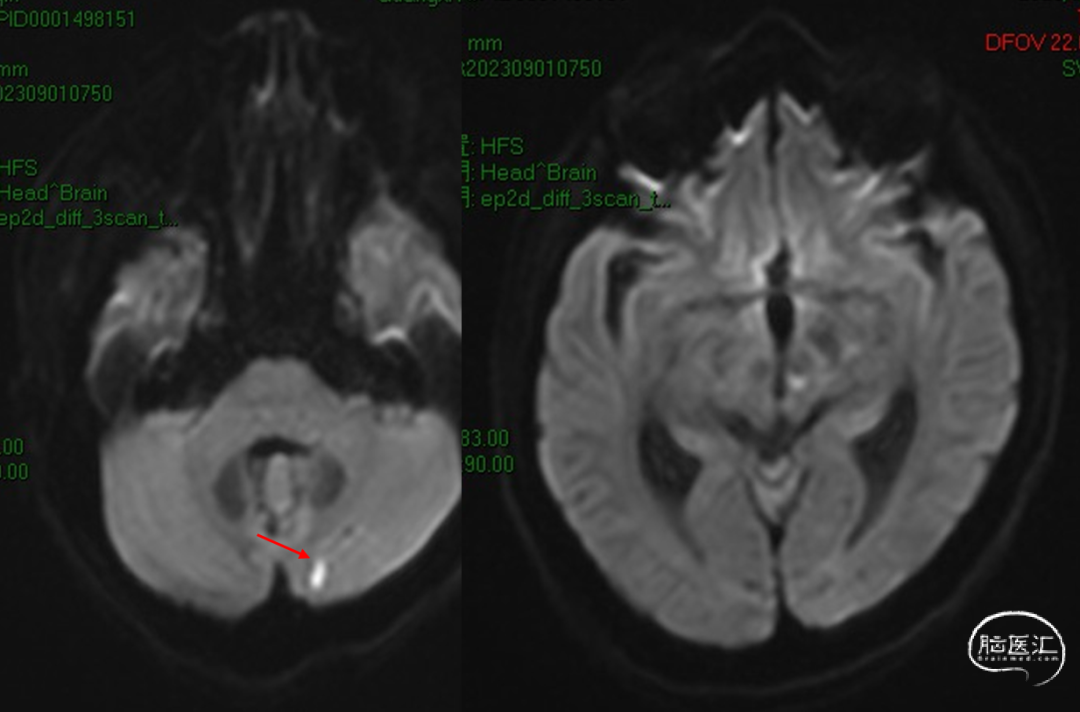

2023-09-01

术后MR未见该中央新发支梗塞

后交通动脉在向后稍内行走的过程中发出两组约2 -8条(以4条为多见)细小的中央支(图1)。前组供应丘脑下部、丘脑腹侧部;视束前部和内囊后肢。后组主要供应丘脑底核。这些中央支之间虽然存在吻合,但其中一支阻塞后,因有效的侧支循环难以建立,故多产生相应供应区的梗死。该病例栓塞假性动脉瘤所在中央支没有症状,考虑为假性动脉瘤导致该中央支缺血耐受和血管代偿。